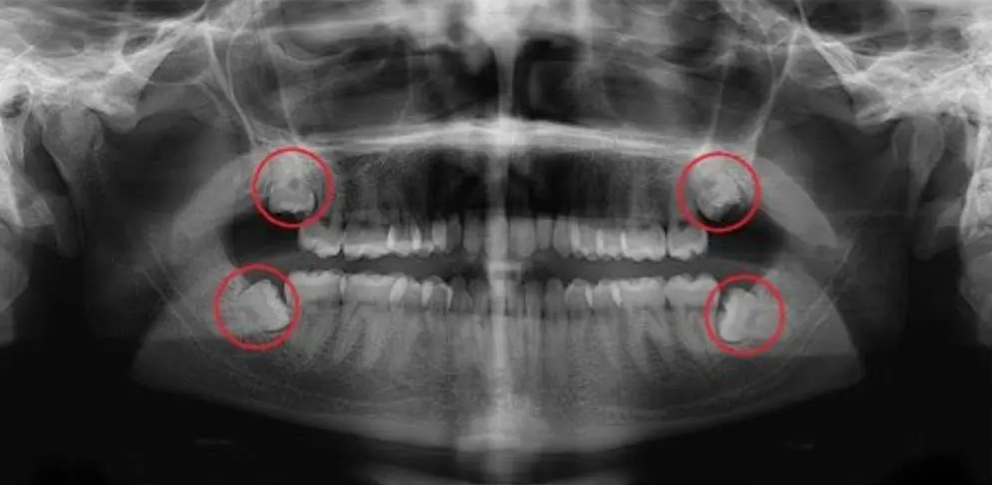

Dents de sagesse

L'extraction des dents de sagesse est souvent préconisée quand il y a un "manque de place" au sein de la mâchoire du patient.

La non-extraction des dents de sagesse peut engendrer des déplacements de dents, des problèmes d'occlusion, ...